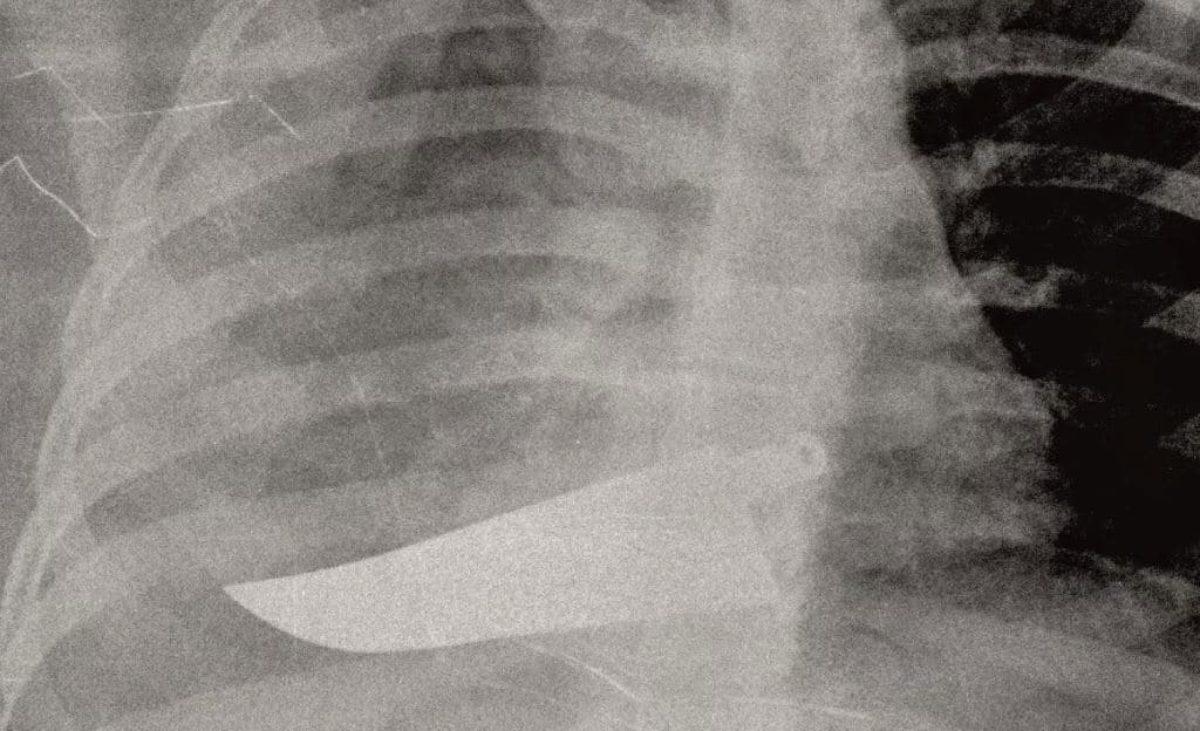

Una delle radiografie in mostra Credit: San Carlo di Milano

Da pugnali conficcati nell'addome a ossa rotte: la violenza sulle donne appare senza filtri nelle radiografie in mostra a Milano

La forza delle immagini contro la violenza sulle donne: una raccolta di foto e radiografie anonime raffigurano la parte più profonda delle vittime di violenza, quella che è stata ferita. Sono le immagini esposte nel rispetto dell’anonimato per scuotere le coscienze sul fenomeno in una mostra che verrà allestita nell’ospedale San Carlo di Milano, da giovedì 21 novembre a domenica 8 dicembre.

L’ideatrice della mostra di sensibilizzazione è la chirurga Maria Grazie Vantadori: “Le donne, spesso, non hanno la forza di raccontare. Ma i corpi e le lesioni parlano per loro, rivelano vertigini di orrore quotidiano. Per questo ho deciso di mostrare la violenza domestica come la vediamo noi al pronto soccorso: ossa rotte, nasi spaccati, occhi pesti, mani fratturate, polsi slogati, gambe rotte, coltellate, bruciature, morsi, segni di strangolamento, ferite da torture con pezzi di vetro. O addirittura un pugnale nella schiena. Lo scenario di una guerra nascosta nelle mura di casa che i numeri non riescono a raccontare”.

I corpi martoriati rivelano la brutalità delle azioni nei confronti delle donne. Fino all’estremo di una donna arrivata al San Carlo con un pugnale conficcato nella schiena. “Sì, quella donna è sopravvissuta, anzi una sopravvissuta. Perché la sfida del nostro centro – dice la chirurga che ha deciso di esporre le radiografie – è non solo soccorrere, ma anche aiutare le pazienti a uscire da quella schiavitù. Chi le accoglie deve saper decodificare i loro silenzi, comprendere quelle le lesioni incompatibili con quanto le donne narrano”.